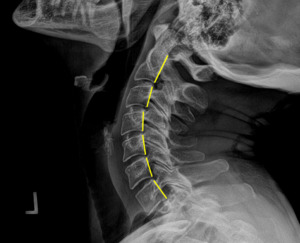

Plain film radiography of the cervical spine showed a grade 1 spondylolisthesis of C4 (Figure 3), mild disc and facet degeneration of C5 (Figure 3), a motion fixation of the C4-C5 vertebrae unit in forward flexion (Figure 4), a retrolisthesis of C3 on extension (Figure 5), and a structural malposition of the craniocervical junction as per Orthospinology measurements. (Figures 6 and 7). Though these are static films and active motion cannot be observed in real-time, motion restriction of the C4-C5 vertebrae unit from neutral to forward flexion position was determined by a lack of spinous separation, a lack of intervertebral foramen expansion, and an absent intersegmental kyphosis of George’s Line.